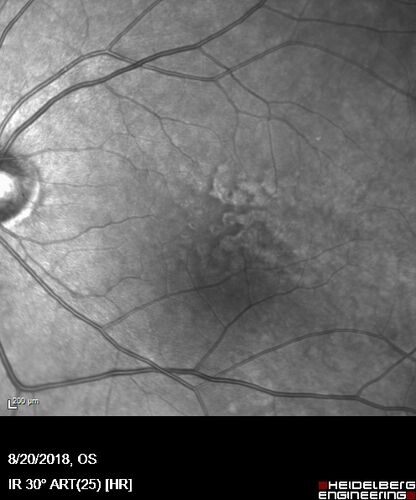

Large and Extensive Macular Drusen

64 year old female with 20/25 vision taking vitamins in for a checkup.